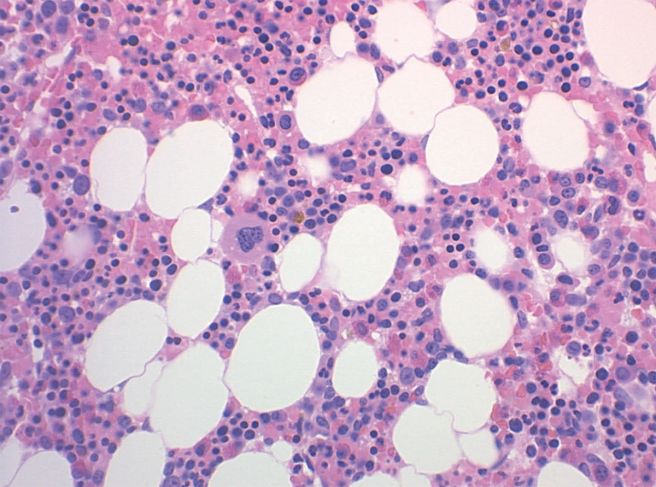

혈소판은 골수에서 만들어지며, 일정 기간이 지나면 새로운 혈소판으로 교체됩니다. 몸은 필요에 따라 혈소판 양을 조절하는데, 상처나 자극이 많아지는 상황에서는 혈소판이 더 적극적으로 활용될 수 있습니다. 혈소판은 응고 과정만 담당하는 것이 아니라, 손상된 부위가 회복될 수 있도록 다음 단계가 진행되도록 돕는 역할도 수행합니다.

골수 기능 저하

혈소판은 골수에서 생성되므로, 골수의 기능이 저하되면 혈소판 생산이 줄어듭니다. 백혈병, 림프종, 재생불량성 빈혈, 항암 치료(화학요법 및 방사선 치료) 등이 이에 해당합니다.